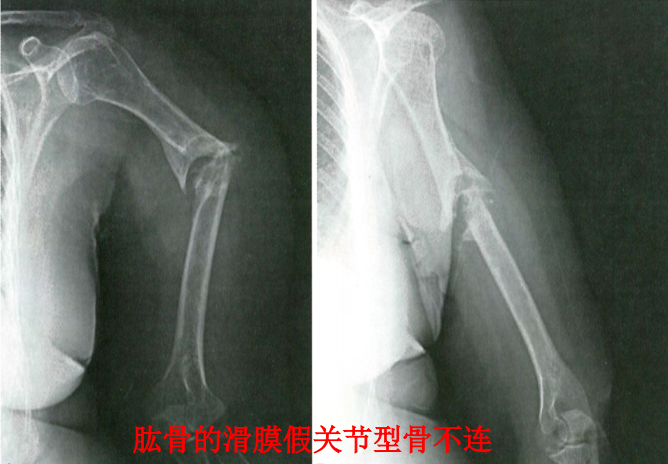

5、假关节性骨不连(假性滑膜关节)

骨端间有充满液体的封闭式假性滑囊,类似于关节结构,可活动。多发生于骨折保守治疗的病人,因固定不稳,早期过度活动造成。